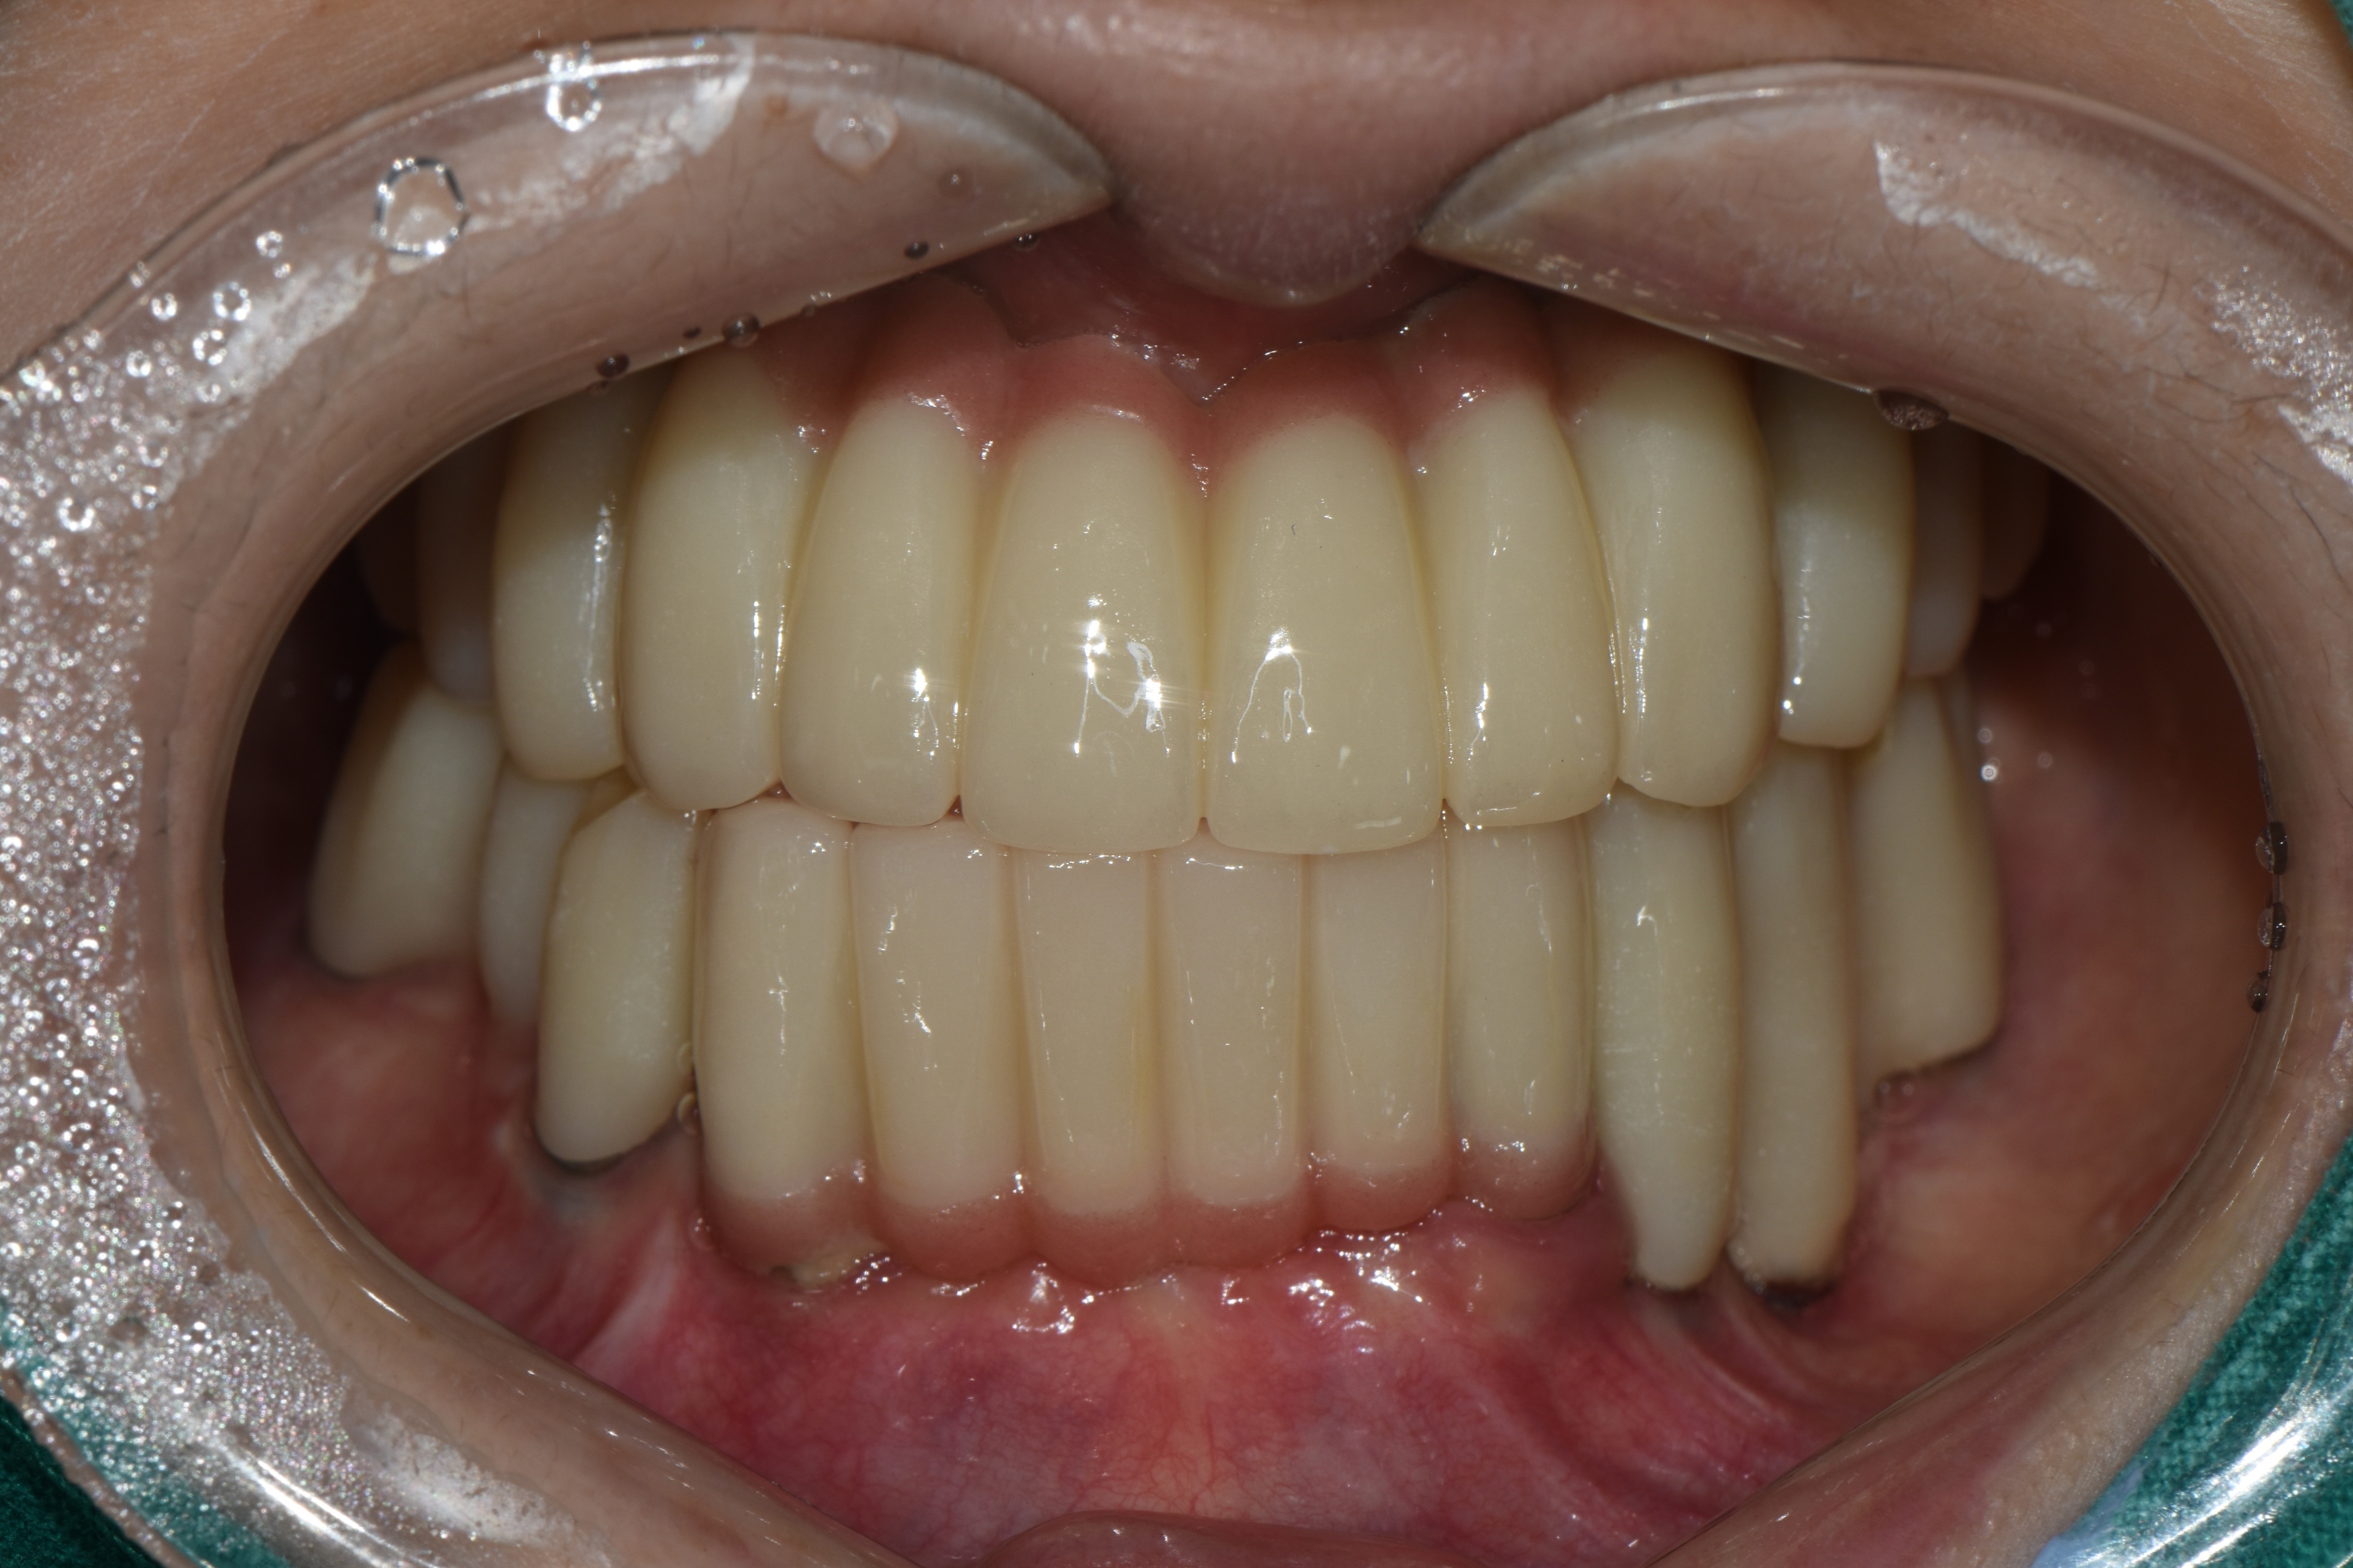

촬영일시: 2025.02.19 [ 치료기간: 2024년 05월 02일 ~2025년 02월 19일 ] ※ 365서울앞선치과의원의 모든 컬럼은 각 진료과 의료진이 직접 작성합니다. 365서울앞선치과의원 임상 케이스 게시물은 환자분께 의학적으로 정확하고 상세한 정보를 드리기 위해 각 진료과 의료진이 직접 작성하며, 모든 증례 사진은 본원 의료진이 직접 시술한 증례를 촬영한 것으로, 의료법 제23조, 제56조에 의거하며 환자분의 동의를 얻어 포스팅에 사용하였습니다. 또한 해당 케이스는 본 환자분의 치료 결과이며, 환자 상태에 따라 치료의 결과는 달라질 수 있습니다. |